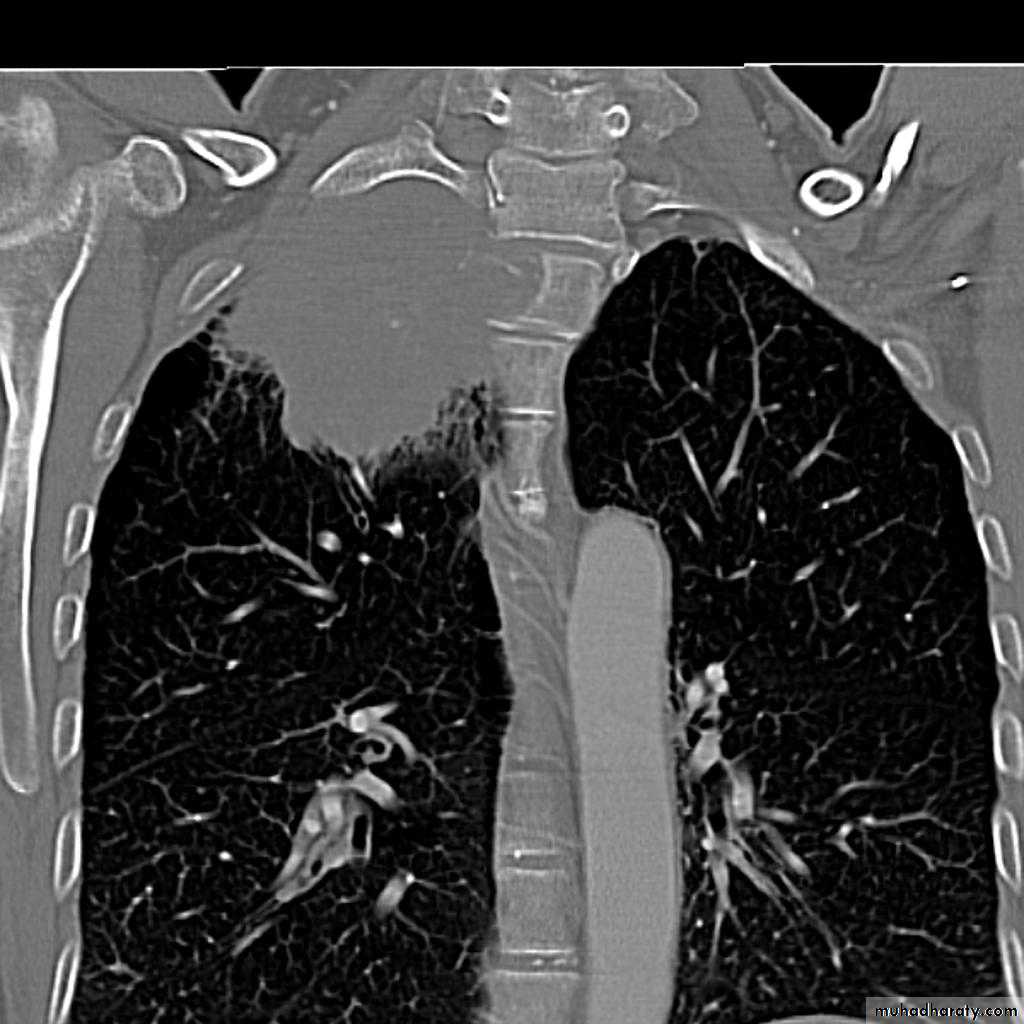

Left upper lobe collapse has distinctive features but can be challenging to identify on chest radiographs by the uninitiated.

Radiographic features

The left upper lobe collapses anteriorly becoming a thin sheet of tissue apposed to the anterior chest wall, and appears as a hazy or veiling opacity extending out from the hilum and fading out inferiorly . It thus reverses the normal slight increase in radiographic density seen as you move down the lung (due to increased thickness of the chest soft tissues).

Parts of the normal cardiomediastinal contour may also be obliterated where the left upper lobe, particularly the lingula abut the left heart border. The anterior parts of the aortic arch are also often obliterated from view.

In some cases the hyperexpanded superior segment of the left lower lobe insinuates itself between the left upper lobe and the superior mediastinum, sharply silhouetting the aortic arch and resulting in a lucency medially. This is known as the luftsichel sign.

The left hilum is also drawn upwards, resulting in an almost horizontal course of the left main bronchus and vertical course of the left lower lobe bronchus.